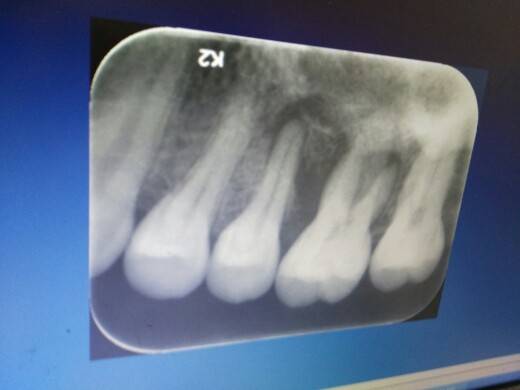

根管终于结束了,跑了4趟,补上陶瓷的,结果:perfect,完美~

第一次去看牙,医生就说,你这颗牙坏时间长了,应该不会疼了,果然,整个过程下来一点都不疼,不知道是医生技术好,还真是坏时间长了就不疼了,反正,不疼了,终于不疼了~~

其实,我觉得大剂量激素时,对牙齿的影响还是很大的,而且我们可能会长期有着激素的影响,所以,我的牙我记得很清楚,刚确诊狼的前两年,牙齿会自行有碎片脱落,慢慢导致有个牙自己掉了半个只剩下根,有个牙坏了个大半……